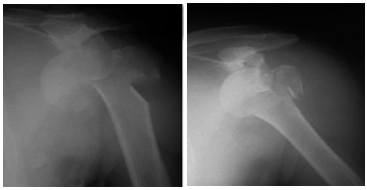

Figure 6 Pre- operative four part fracture dislocation.

Figure 7 Immediate postoperative films showing congruous reduction, stabilized greater tuberosity and contained head of humerus.

Figure 8 6 months postoperative films-good contained head of humerus, no signs of avascular necrosis and patient had excellent shoulder function.